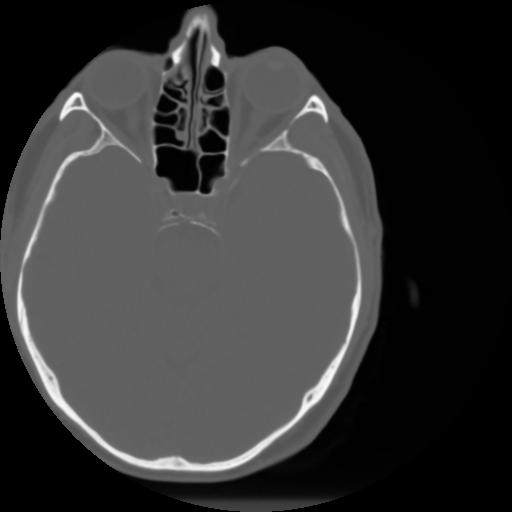

3 CEREBRO,,Axial,3.0,CEREBRO,,